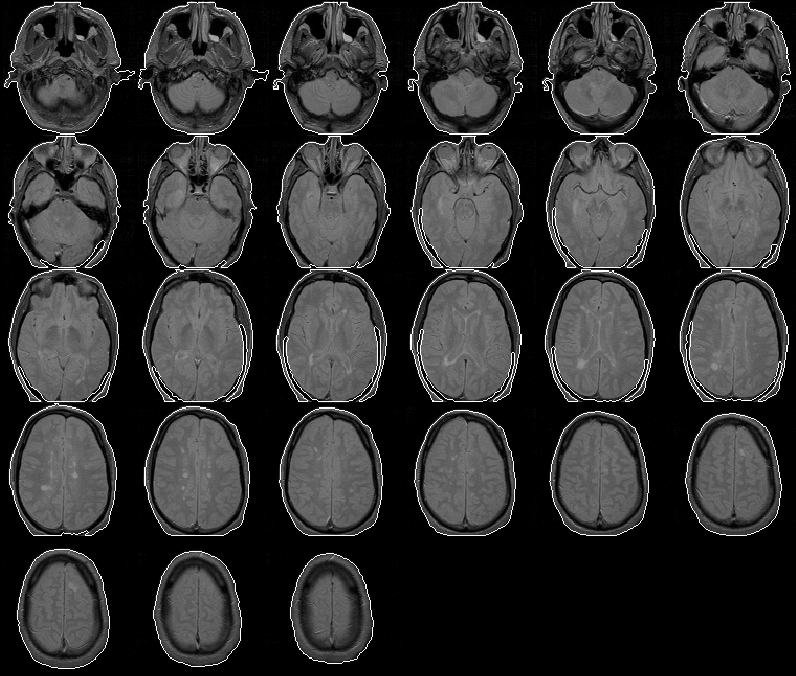

The Segment Head process produces a head mask for Data Set 4 with no significant errors. The head mask is overlaid on the PD-weighted volume in Figure 8.9.

Figure 8.9: The head mask for MRI Data Set 4 overlaid on the PD-weighted scan.

The head mask for Data Set 5 is overlaid on the PD-weighted volume in Figure 8.10. The mask contains minor errors similar to those in the head mask of Data Set 2.

Figure 8.10: The head mask for MRI Data Set 5 overlaid on the PD-weighted scan.